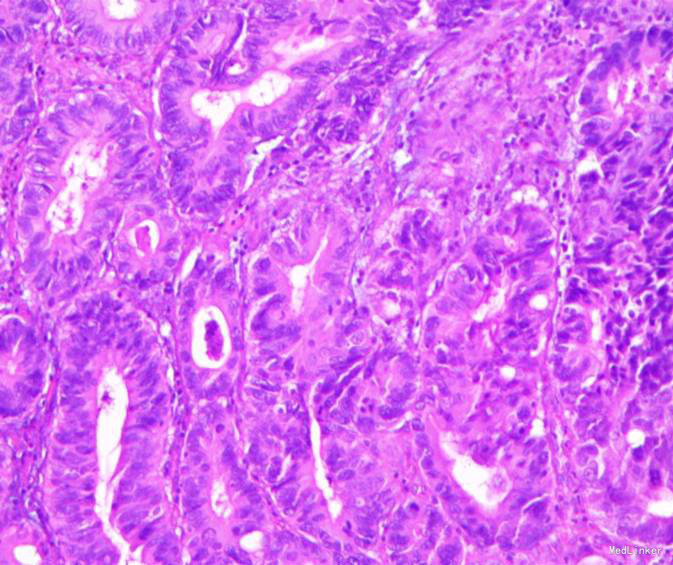

随访:出院后2周,电话随访患者,一般情况良好,无不适主诉。 讨论:该患者胃镜见一胃窦前壁粘膜隆起,表面粘膜粗糙,病理示:慢性萎缩性胃炎,伴部分腺体中重度不典型增生,局灶重度不典型增生,超声胃镜病灶未突破粘膜下层,有胃ESD手术指征,故行全麻下胃ESD术。术后病理:胃窦前壁肿瘤:腺上皮高级别上皮同瘤,部分癌变,病变大小1.5*1.1*0.3cm,基底及切缘未见癌。说明手术成功,切缘及基底均无肿瘤侵及。对于早癌患者我们完全可以通过采用ESD方法治愈患者,胃镜下切除早癌较腹腔镜创伤更小。我和患者解释时是这样说的:腹腔镜是微创,而我们内镜下ESD则是微微创。